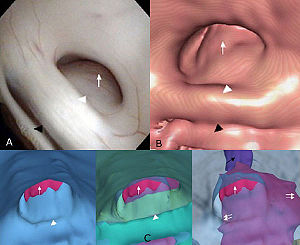

Low-cost Interactive Image-based Virtual Endoscopy for the Diagnosis and Surgical Planning of Suprasellar Arachnoid Cysts

|

Publication: World Neurosurg. 2015 Dec 27. PMID: 26732948

Institution: Department of Neurosurgery, People's Liberation Army General Hospital, Beijing, China. Background/Purpose: OBJECTIVE: To investigate the feasibility and reliability of virtual endoscopy (VE) as a rapid, low-cost and interactive tool for suprasellar arachnoid cysts (SACs) diagnosis and surgical planning. Methods: 18 SACs patients treated with endoscopic ventriculocystostomy were recruited, and same number of endoscopic third ventriculostomy treated patients was randomly selected as VE reconstruction control group. After loading their DICOM data into free software 3D Slicer, VE reconstruction was independently performed by 3 blinded clinicians and the time required for each reconstruction was recorded. Other 3 blinded senior neurosurgeons interactively graded the visibility of VE by watching video recordings of endoscopic procedures. Based on the visibility scores, Receiver Operating Characteristic (ROC) curve analysis was used to investigate the reliability of VE to diagnose SACs, and the Bland-Altman plot was employed to assess the VE's reliability for surgical planning. In addition, intra-class correlation coefficient (ICC) was calculated to estimate the consistency among the results of 3 reconstructing performers. Results: All 3 independent reconstructing performers successfully completed VE simulation for all cases, and the average reconstructing time was 10.2±9.7 minutes. The area under ROC curve of cyst's visibility score was 0.96, implying its diagnostic value of SACs. Bland-Altman plot indicated good agreement between VE and intraoperative viewings, suggesting the VE's anatomical accuracy for surgical planning. In addition, ICC was 0.81, which revealed excellent inter-performer consistency of our simulation method. Conclusion: This study substantiated the feasibility and reliability of VE as a rapid, low-cost and interactive modality for SACs diagnosis and surgical planning. |